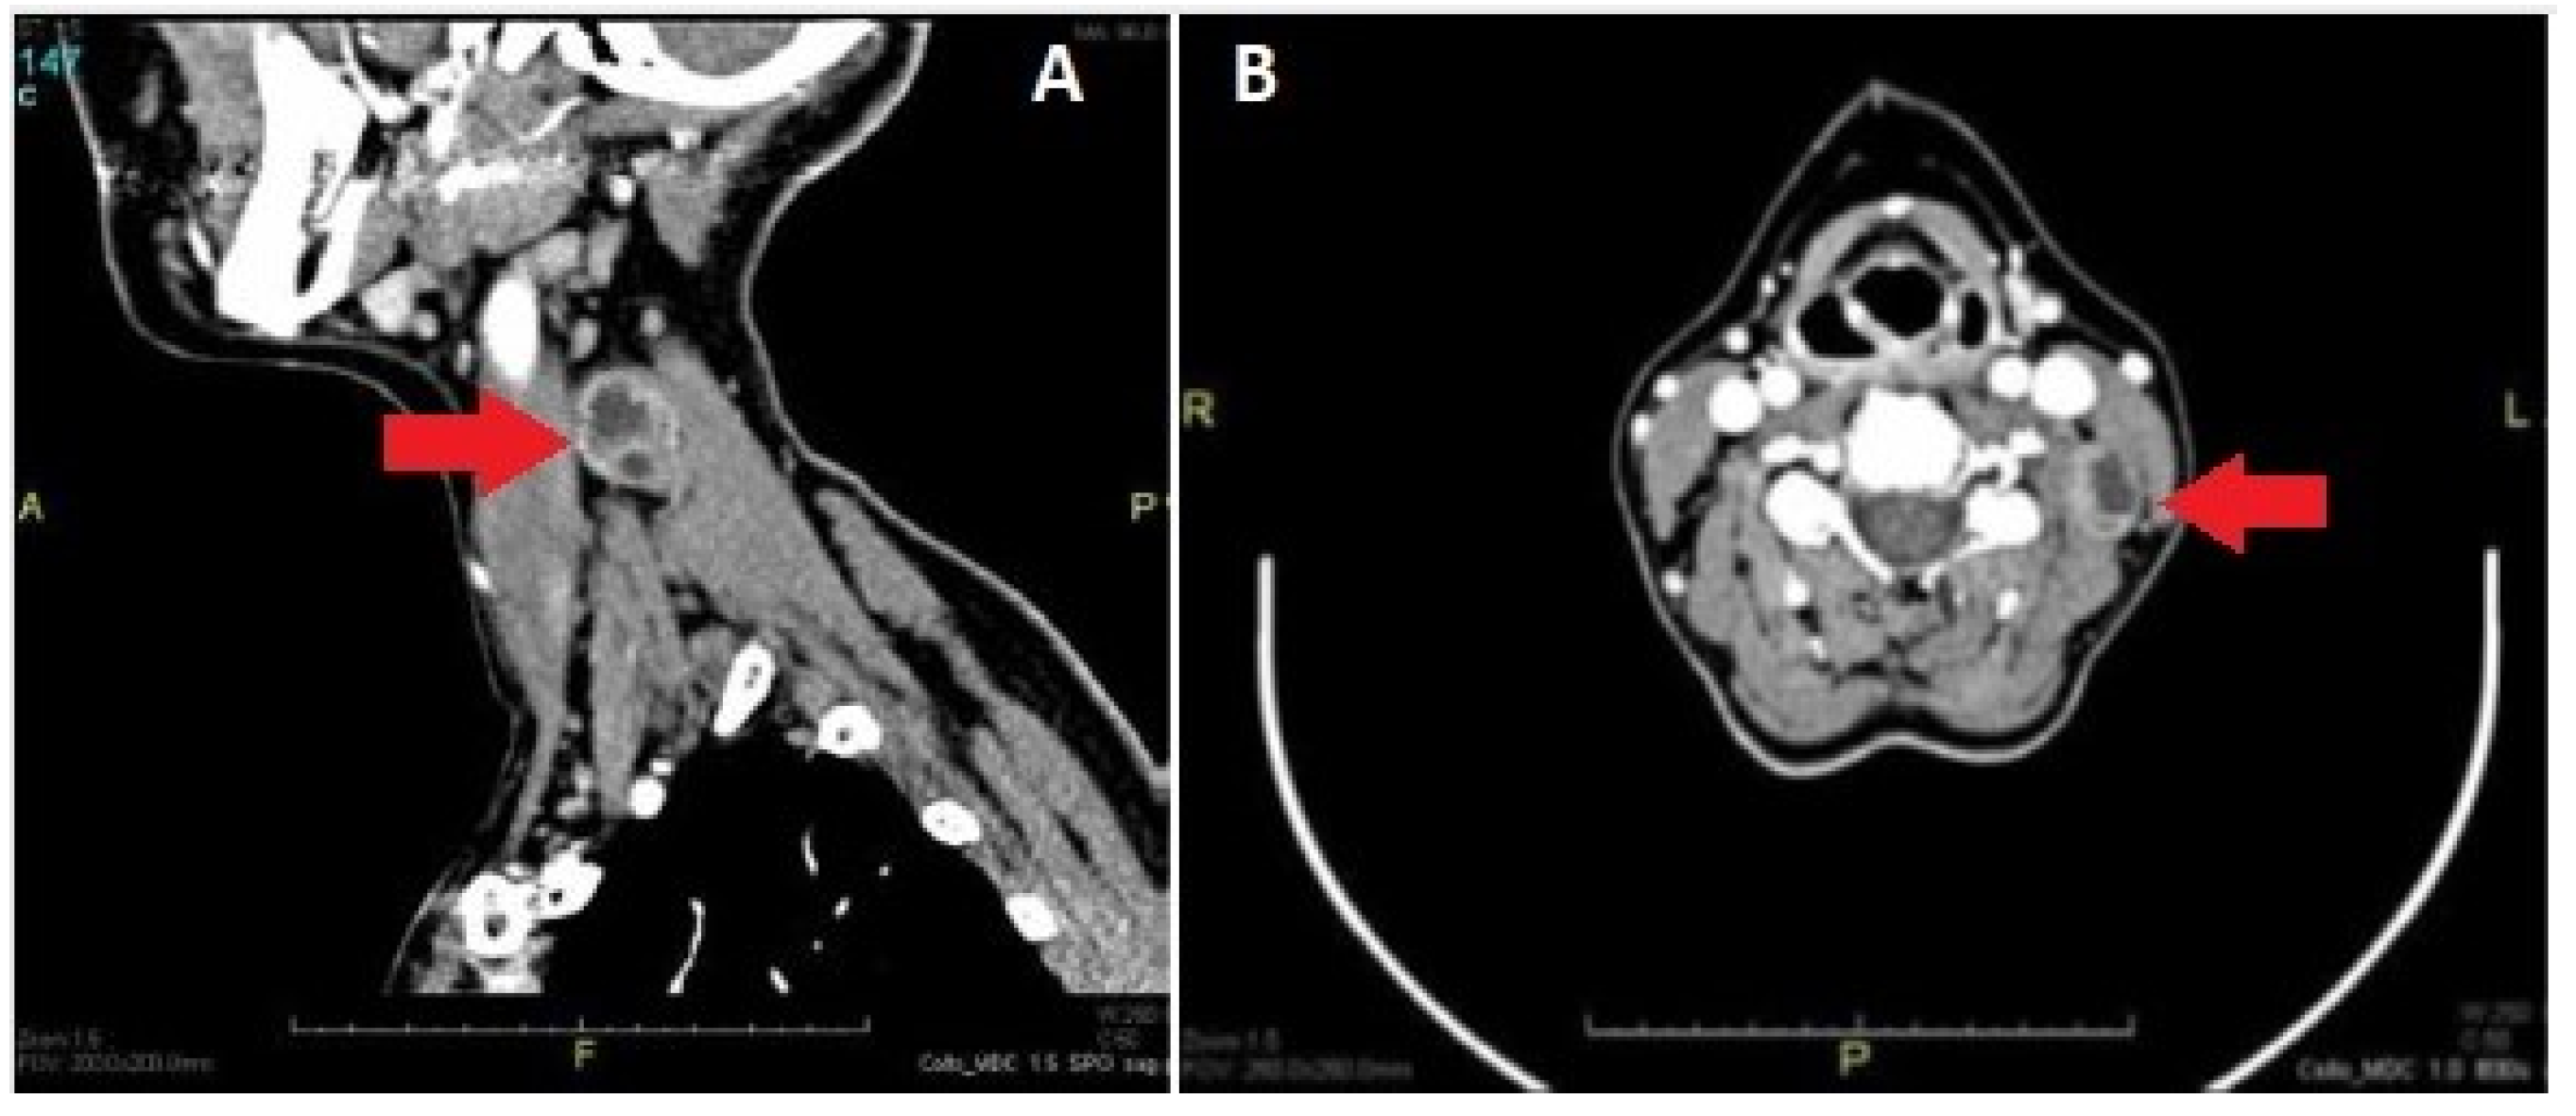

- Anil, G.; Tan, T.Y. CT and MRI evaluation of nerve sheath tumors of the cervical vagus nerve. Am. J. Roentgenol. 2011, 197, 195–201. [Google Scholar] [CrossRef]

- Furukawa, M.; Furukawa, M.K.; Katoh, K.; Tsukuda, M. Differentiation between schwannoma of the vagus nerve and schwannoma of the cervical sympathetic chain by imaging diagnosis. Laryngoscope 1996, 106, 1548–1552. [Google Scholar] [CrossRef] [PubMed]